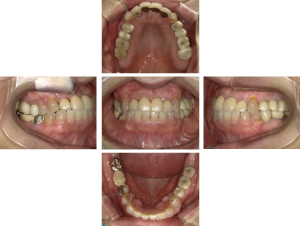

50代 インプラント治療(右上3左上3のみGBR)

| 年代・性別 | 50代・男性 |

| 主訴 | 入れ歯が合わず毎日ヨーグルトしか食べることができないので、しっかり咬めるインプラントにしたい。 |

| 部位 | 右下⑦⑥5④ 上顎③2①①2③ 左下67 |

| 治療期間 | 約9ヶ月 |

| 費用 | ¥4,273,500(税込) |

| 副作用・リスク |

|